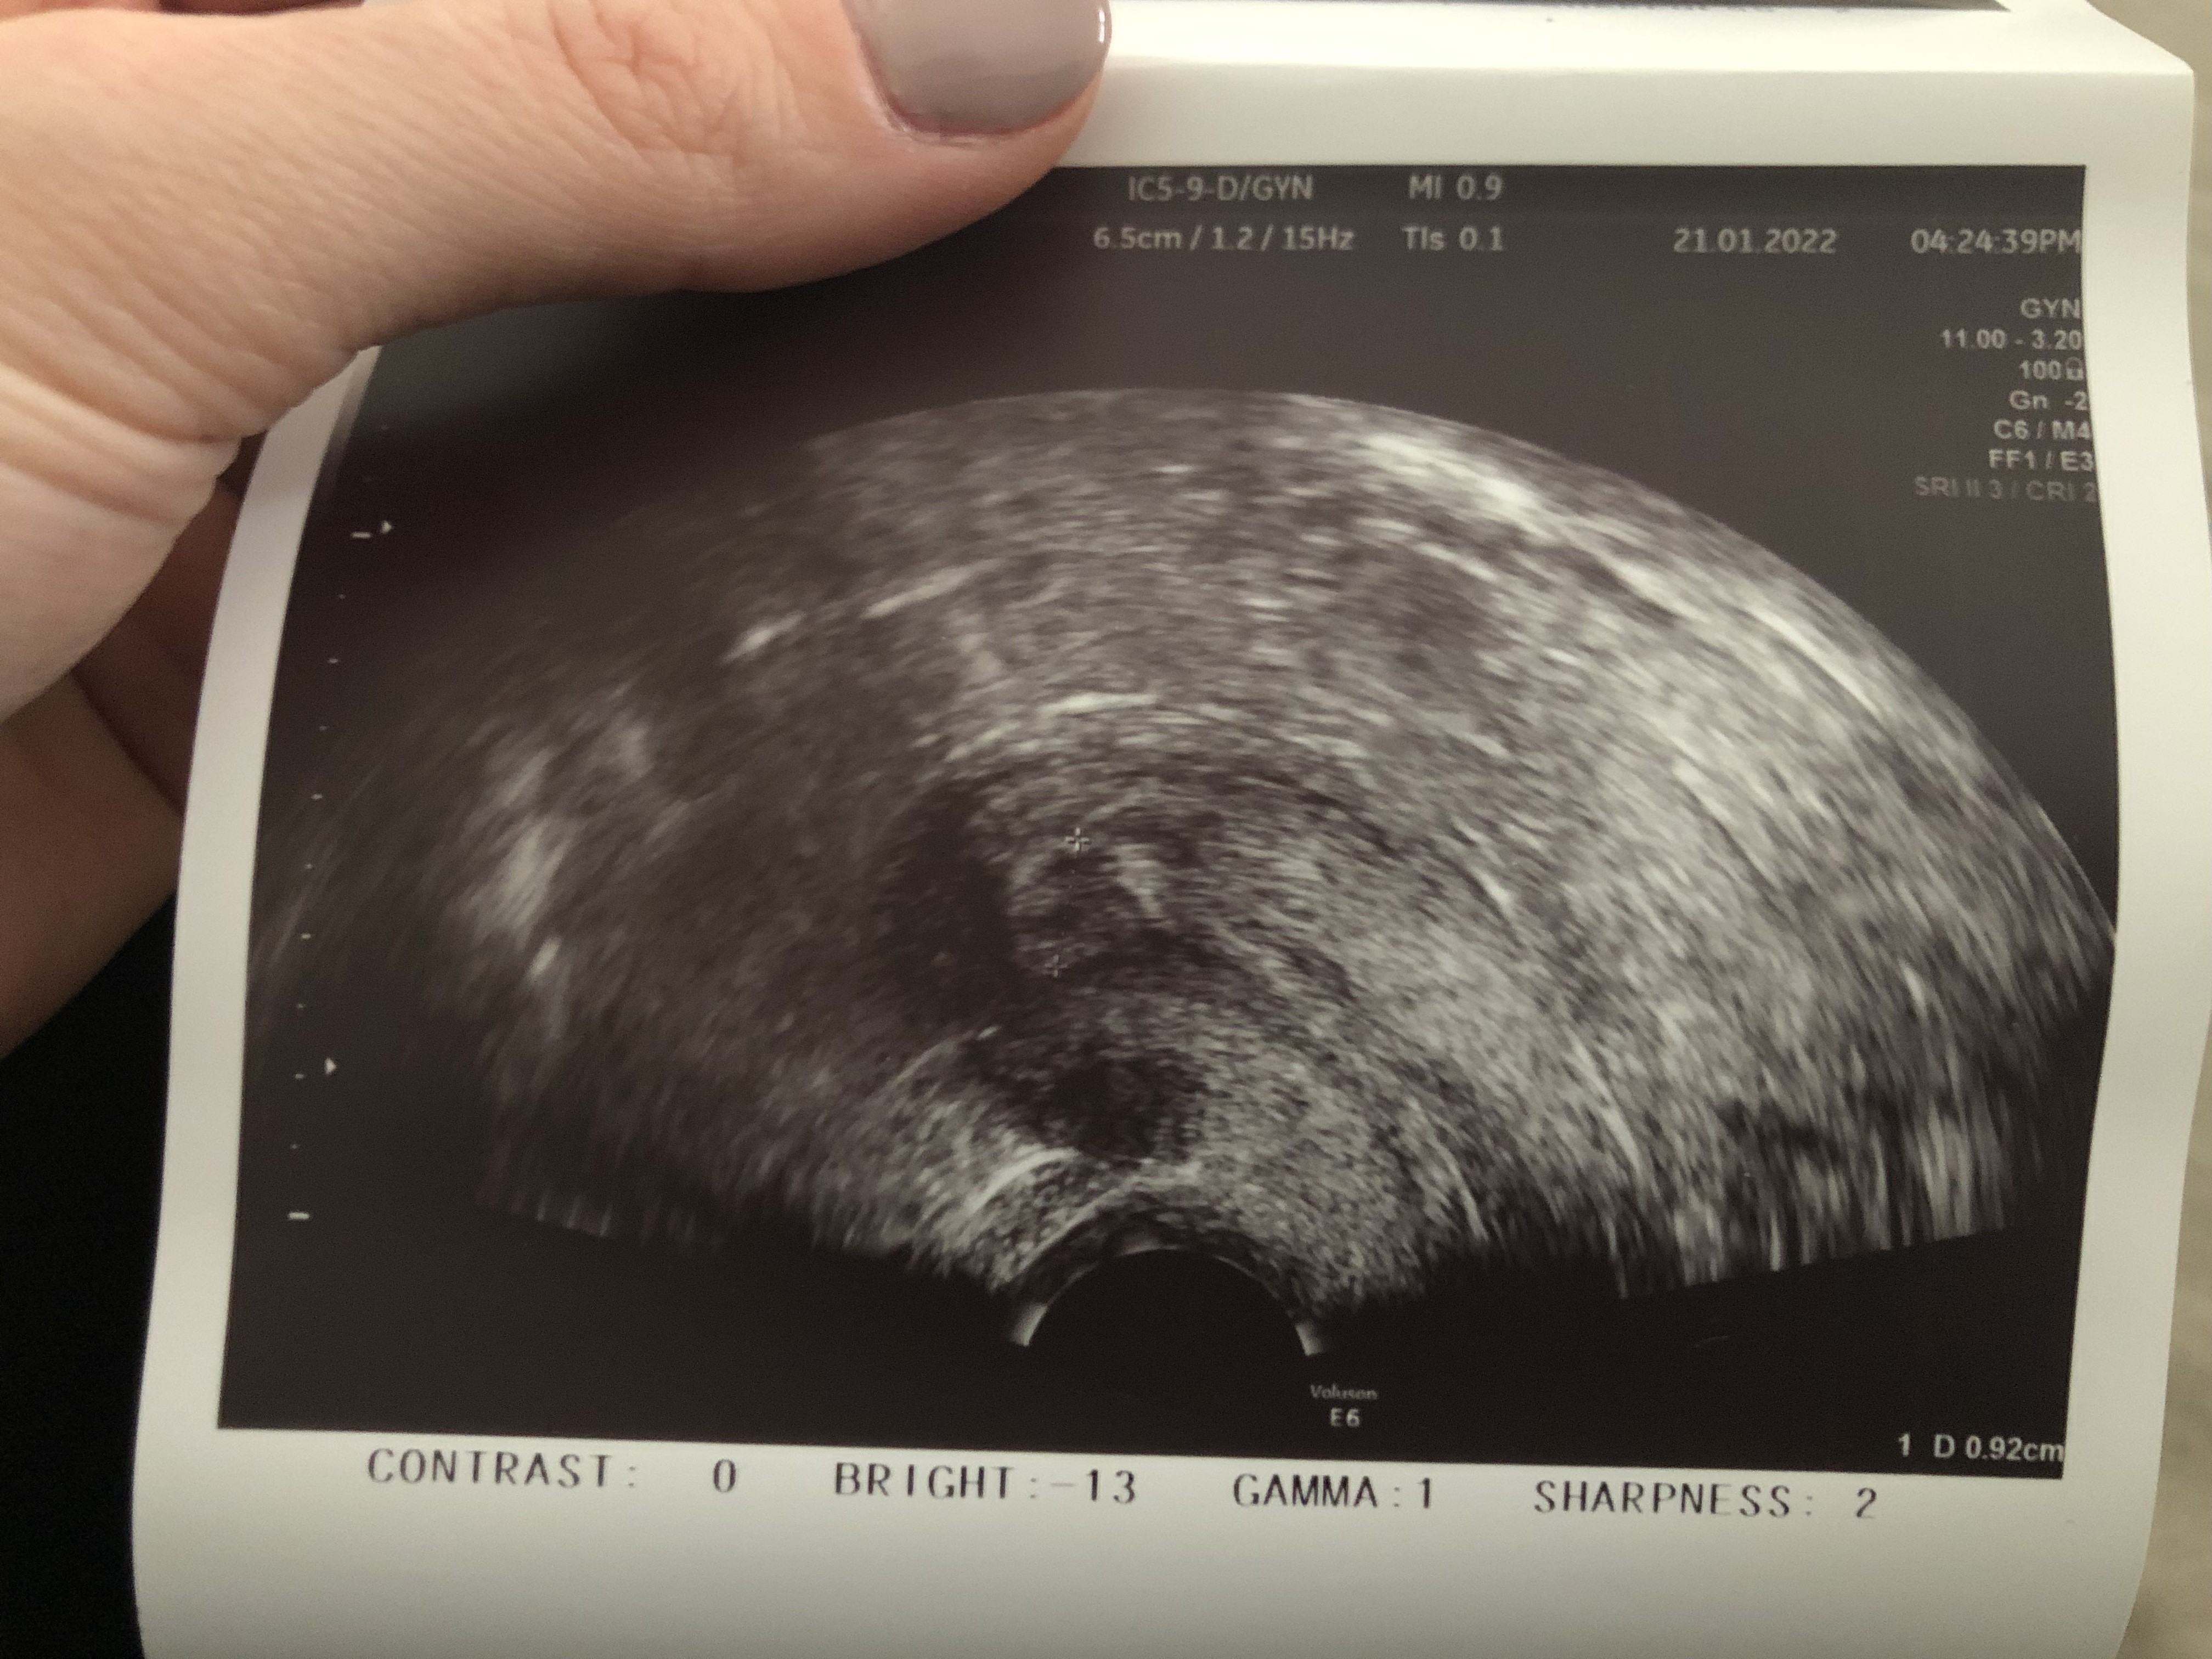

Wrzucam akurat z dnia po owu 0,92 jest o ile coś widaćA pokaż całość zdjęcia z tym wymiarem 0,75 bo ucięłaś połowę. To może być oczywiście endometrium.

Szczerze Ci powiem pierwszy raz widzę taki obraz endometrium, więc nie mam bladego pojęcia czy to to. Ale z drugiej strony nie jest to ani jajnik ani nic innego. Szkoda że nie dostałaś opisuWrzucam akurat z dnia po owu 0,92 jest o ile coś widać![]()